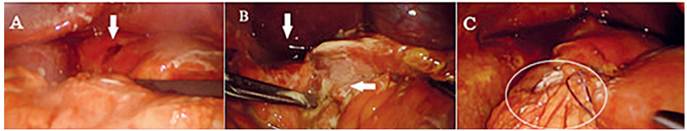

Dados los hallazgos, se decidió llevar al paciente a cirugía, la cual se realizó posicionandolo en decúbito supino con 30° de Trendelemburg invertido. Se insertó un trocar de 10 mm por el puerto umbilical, y tres de 5 mm en flanco derecho, hipocondrio izquierdo y epigástrico. Se insufló neumoperitoneo a 11 mm/Hg de presión y flujo de 6 L/min. Se encontró peritonitis química generalizada con líquido turbio, UDP a nivel del bulbo y membranas fibrino-purulentas generalizadas (Figura 2). Se aspiró el líquido peritoneal, se desbridaron los bordes de la úlcera y se cerró con tres puntos simples de poliglactina 4-0 dejando los cabos largos, con los que se fijó el colgajo pediculado de epiplón sobre la sutura duodenal y se lavó la cavidad abdominal con solución salina, sin necesidad de dejar dren.

En úlceras de menos de 2 cm se sugiere realizar reparaciones primarias, siendo el parche de Graham una opción viable en casos específicos. No existe evidencia suficiente para elegir el cierre primario sobre el parche de Graham en la reparación de la UDP, por lo que el abordaje se basa en el criterio del cirujano. En nuestro paciente se realizó la corrección quirúrgica con cirugía mínimamente invasiva con parche de Graham, con el fin de disminuir el riesgo de dehiscencia en un tejido con edema asociado. El uso de colgajos sin vascularización tiene mayor riesgo de necrosis, por lo que es poco utilizado 25.